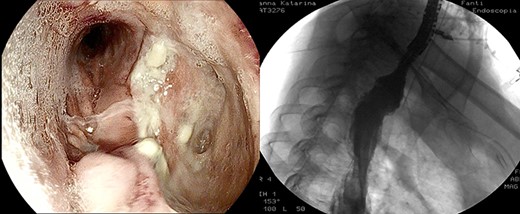

After the 14th session, the endoscopic evaluation showed a significantly cleaner and smaller cavity (1 cm). Two esophageal fully covered SEMS (Taewoong Niti-S Beta Stent) allowed the patient to have a liquid diet while the leak was safely healing: the stents were subsequently placed and kept for 3 weeks each. Endoscopy and esophagram were performed after SEMS removal, and they demonstrated leak resolution, with a tiny persistent depression at the site (Fig. 4). The patient has not had symptoms of recurrent fistula formation for over 6 months.